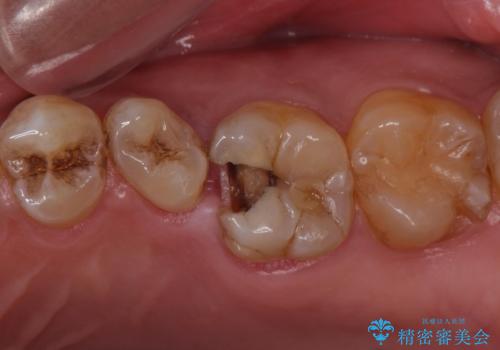

- 左上の奥歯を何とか保存していた患者様です。

今回、残していた歯根から歯茎が大きく腫れ、長期的な予後を期待できないことを考慮し、抜歯してブリッジでの治療を行いました。